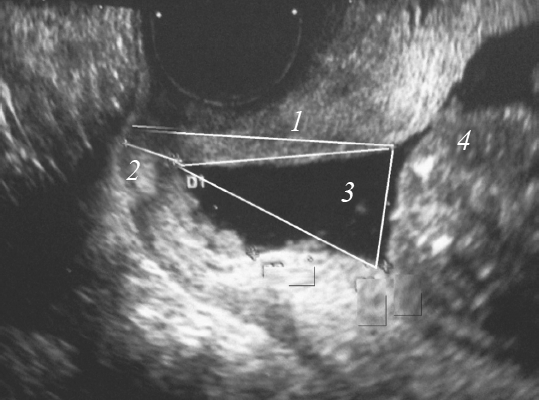

Диагноз ИЦН устанавливали на основании анамнестических данных, клинических и инструментальных методов исследования. При влагалищном исследовании оценивали длину вагинальной части шейки матки, консистенцию, положение шейки матки, состояние наружного маточного зева, проходимость цервикального канала. Диагноз подтверждали общепринятыми ультразвуковыми критериями (сохраненная часть шейки матки, состояние внутреннего зева, раскрытие цервикального канала) [9] (рис. 1).

Рис. 1. Беременность 20 недель, истмико-цервикальная недостаточность: 1 — общая длина шейки матки; 2 — сохраненная часть шейки матки; 3 — воронкообразное открытие внутреннего зева; 4 — предлежащая часть плода

Fig. 1. Pregnancy 20 weeks SI, 1 – the total length of the cervix, 2 – the retained part of the cervix, 3 – the funnel – shaped opening of the inner throat, 4 – the adjacent part of the fetus